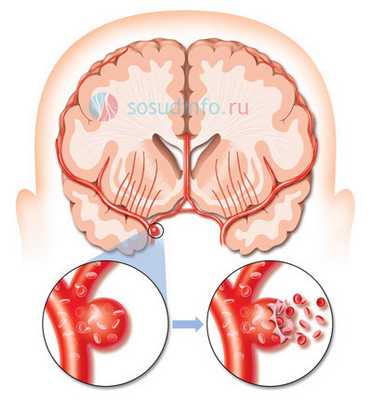

Аневризма мозговых сосудов - очень коварная патология. Долгое время она может протекать бессимптомно, и ее обладатель даже не догадывается о наличии аномалии. Вместе с тем, любая аневризма несет в себе риск кровоизлияния, последствия от которого могут стать фатальными, поэтому операция на аневризму - единственно верное решение при ее обнаружении.

Аневризма мозговых сосудов чаще имеет артериальное строение, может располагаться в самых разных отделах черепа и иметь размеры от микроскопических до гигантских. Конечно, риск разрыва несоизмеримо выше при крупном образовании, но и при мелких аневризмах он есть.

Из всех кровоизлияний внутри черепа субарахноидальное - одно из самых тяжелых, а причиной его в 85% случаев становится сосудистая мальформация. Кровь при этом проникает под мягкую мозговую оболочку, сдавливает мозг, нарушает движение ликвора, провоцирует тяжелые неврологические нарушения, а дислокация структур ствола мозга имеет высокий риск гибели в острейшем периоде заболевания.

разрыв аневризмы мозга